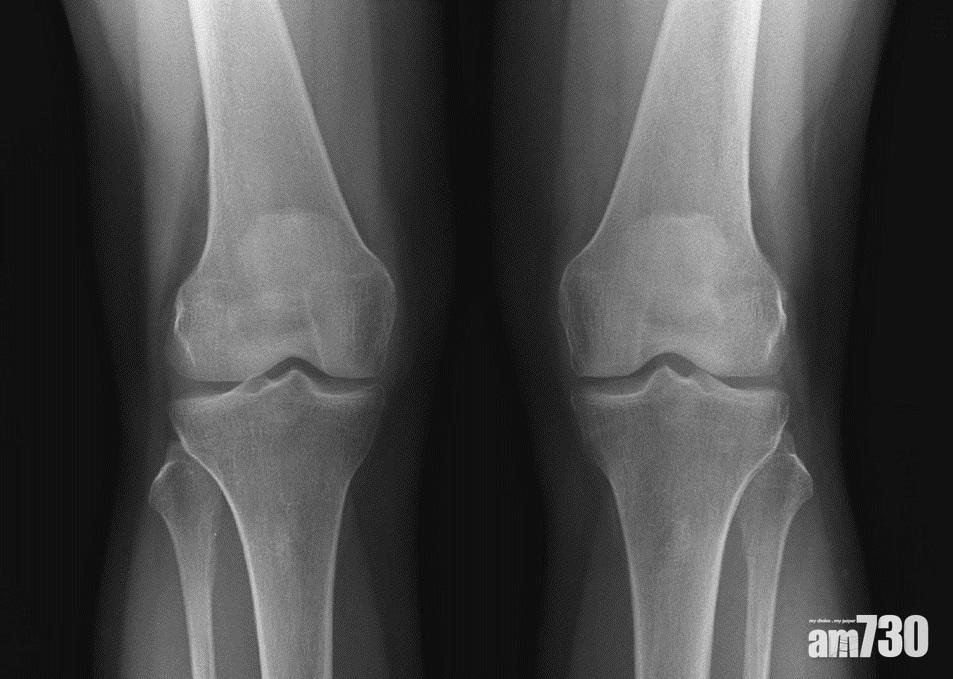

退化性關節(左)的軟骨層遭磨蝕,距離較正常的關節(右)少,嚴重可出現骨磨骨的情況。(圖片由醫生提供)